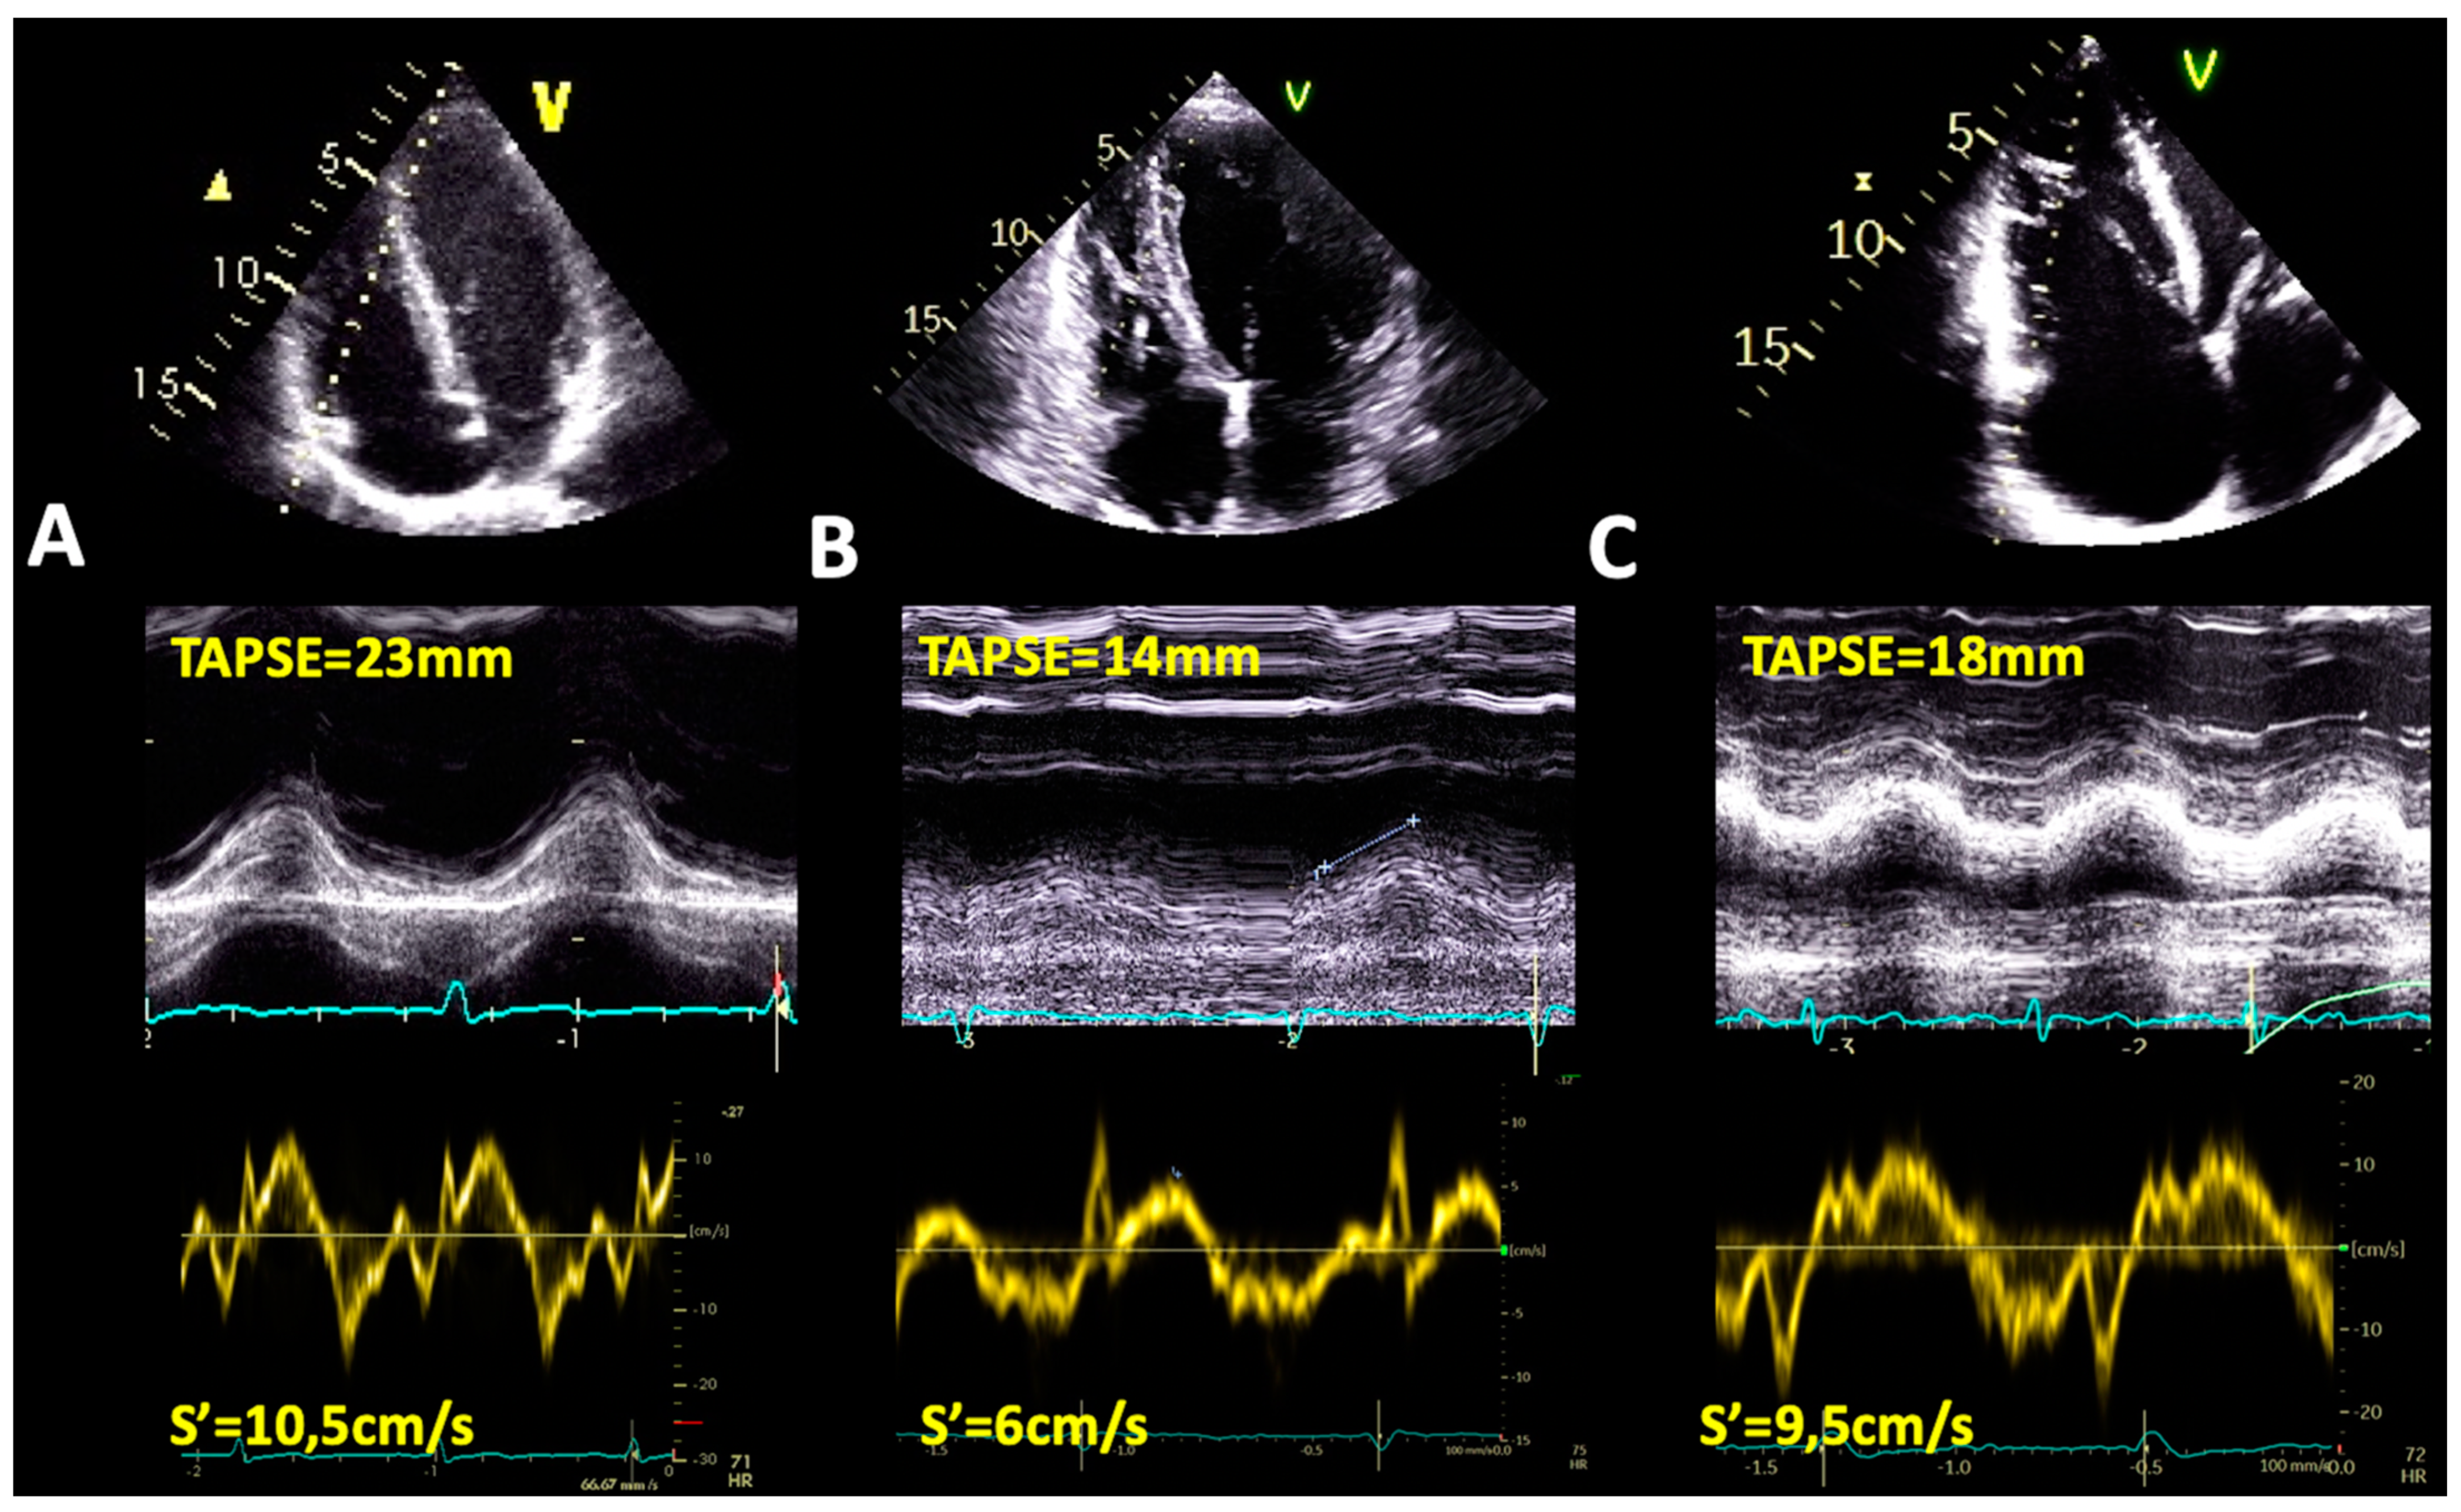

4.1.1. Tricuspid Annulus Plane Systolic Excursion by M-Mode Echocardiography

4.1.2. S’ Wave Velocity by Tissue Doppler Imaging